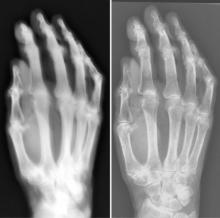

Researchers recently tested first-generation X-ray equipment from 1896 and found it produced radiation doses and exposure times that were vastly higher than those of today’s systems, according to a study published online and in the May print edition of Radiology.